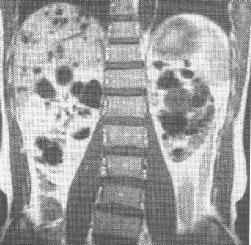

多囊腎 CT掃描 |

3、CT掃描:在過去用於確診多囊腎的非侵入性診斷技術中,CT是最理想的。多發囊腫薄薄囊壁內充滿的囊液及較正常增大了的腎臟,使這一成像方式在確診時極為精確(95%)。

多囊腎 CT掃描